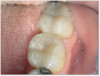

Figure 6a through Figure 6d show a procedure using a bulk fill packable as an interproximal Class 2, without using a bulk fill flow and not done with the snowplow technique to see how well the composite adapted to the margin. A light curable resin-modified calcium silicate liner (Bisco TheraCal LC) was used to perform an indirect pulp cap. A packable bulk fill composite was applied as a single increment layer to successfully restore the tooth. The material (Kerr SimpliShade Bulk Fill Packable) provided good adaptation to the tooth without gaps or polymerization stress lines and demonstrated great polishability and blendability. The patient reported no post operative sensitivity or discomfort in the 9 months after the restoration was performed. Sensitivity can be a concern if a composite is subjected to too much polymerization shrinkage.

Fig 6a. A procedure using a bulk fill packable as an interproximal Class 2, without using a bulk fill flow and not done with the

snowplow technique. A light curable resin-modified calcium silicate liner (Bisco TheraCal LC) was used to perform an indirect pulp cap. A

packable bulk fill composite was applied as a single increment layer. The material (Kerr SimpliShade Bulk Fill Packable) was used to provide

good adaptation to the tooth without gaps or polymerization stress lines and demonstrated great polishability and blendability.